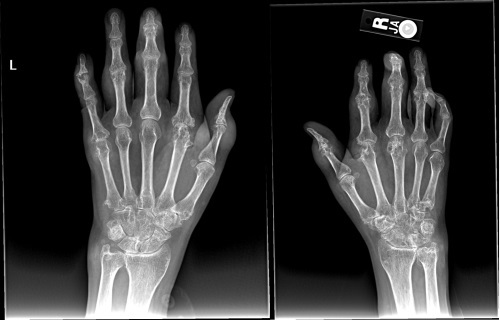

What are 6 radiological features of gout?